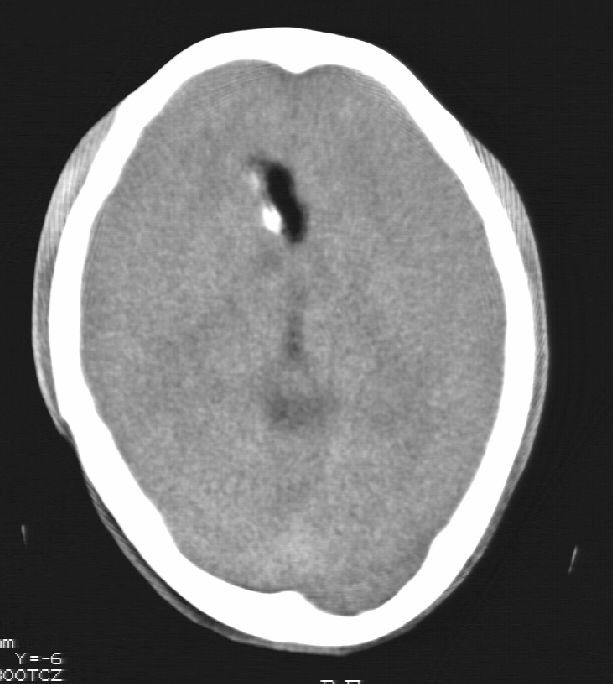

患者男,22岁,因外伤入院,低密度影ct值约-120hu。

胼胝体发育不全合并 透明隔缺如 、脂肪瘤。

胼胝体发育不全合并脂肪瘤;建议必要时行mri检查。

脑水肿,头皮下血肿,胼胝体发育不全、合并脂肪瘤及钙化;建议必要时行mri检查。

胼胝体发育不全、合并脂肪瘤及钙化。